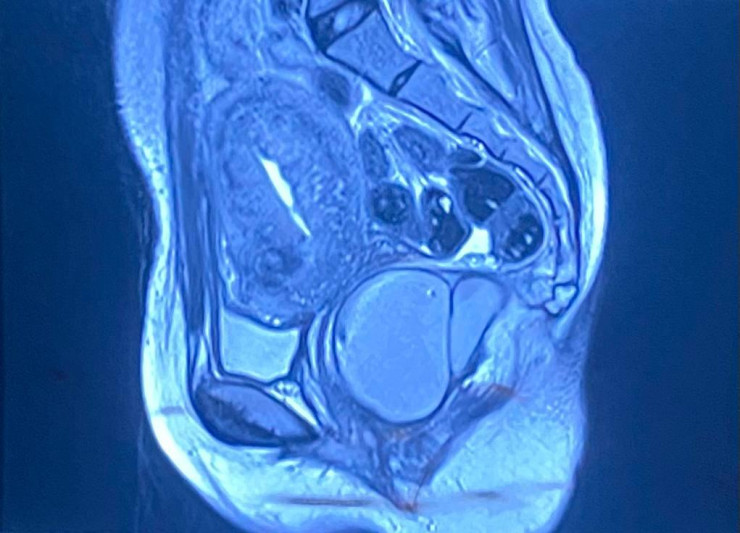

Огромную кисту размером с голову ребенка удалили у девушки алматинские хирурги, передает корреспондент Tengrinews.kz. Операция была проведена в малом тазу.

По словам заведующего отделением колопроктологии городской клинической больнице № 7 Алматы Марата Каленбаева, киста огромного размера 18 на 16 сантиметров округлой формы отличалась редким расположением в пресакральной области с локализацией в малом тазу и бессимптомным течением. Киста мешала опорожнению естественным путем, молодая девушка страдала от постоянного выраженного дискомфорта в области прямой кишки.

"Пресакральная киста - это аномальная полость или кармашек, расположенный в области пресакрального пространства, которое находится между копчиком и прямой кишкой. Данная патология довольно редкая, таких пациентов встречается 1 случай на 40 тысяч населения. Как правило, пресакральная киста выявляется на МРТ или УЗИ органов малого таза размерами 2 сантиметра и чуть более, а в данном случае она аномально большого размера", - рассказал хирург-колопроктолог.